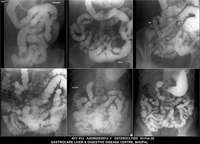

Section: ENTEROCLYSIS Total: 205 images

BaM Enteroclysis Loopogram BaE Fistulogram Urethrogram HSG